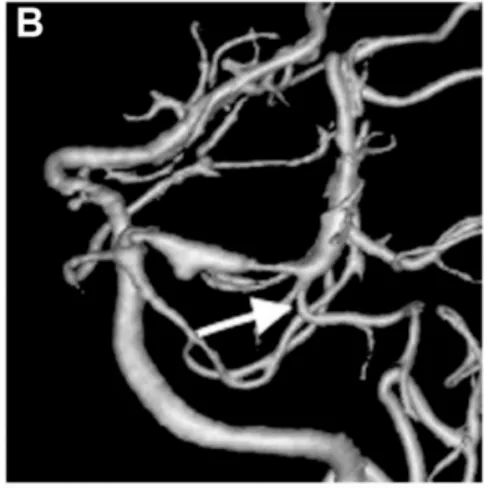

出血后第18天,待陈先生状况稳定后,医生进行了脑血管造影检查(图B)。结果显示,左侧大脑后动脉P1-P2段出现异常扩张伴狭窄——这是夹层动脉瘤的特征表现。

出血后18天血管造影显示左侧P1-P2段扩张伴狭窄特征,颞后动脉自狭窄病变远端发出(箭头标注)